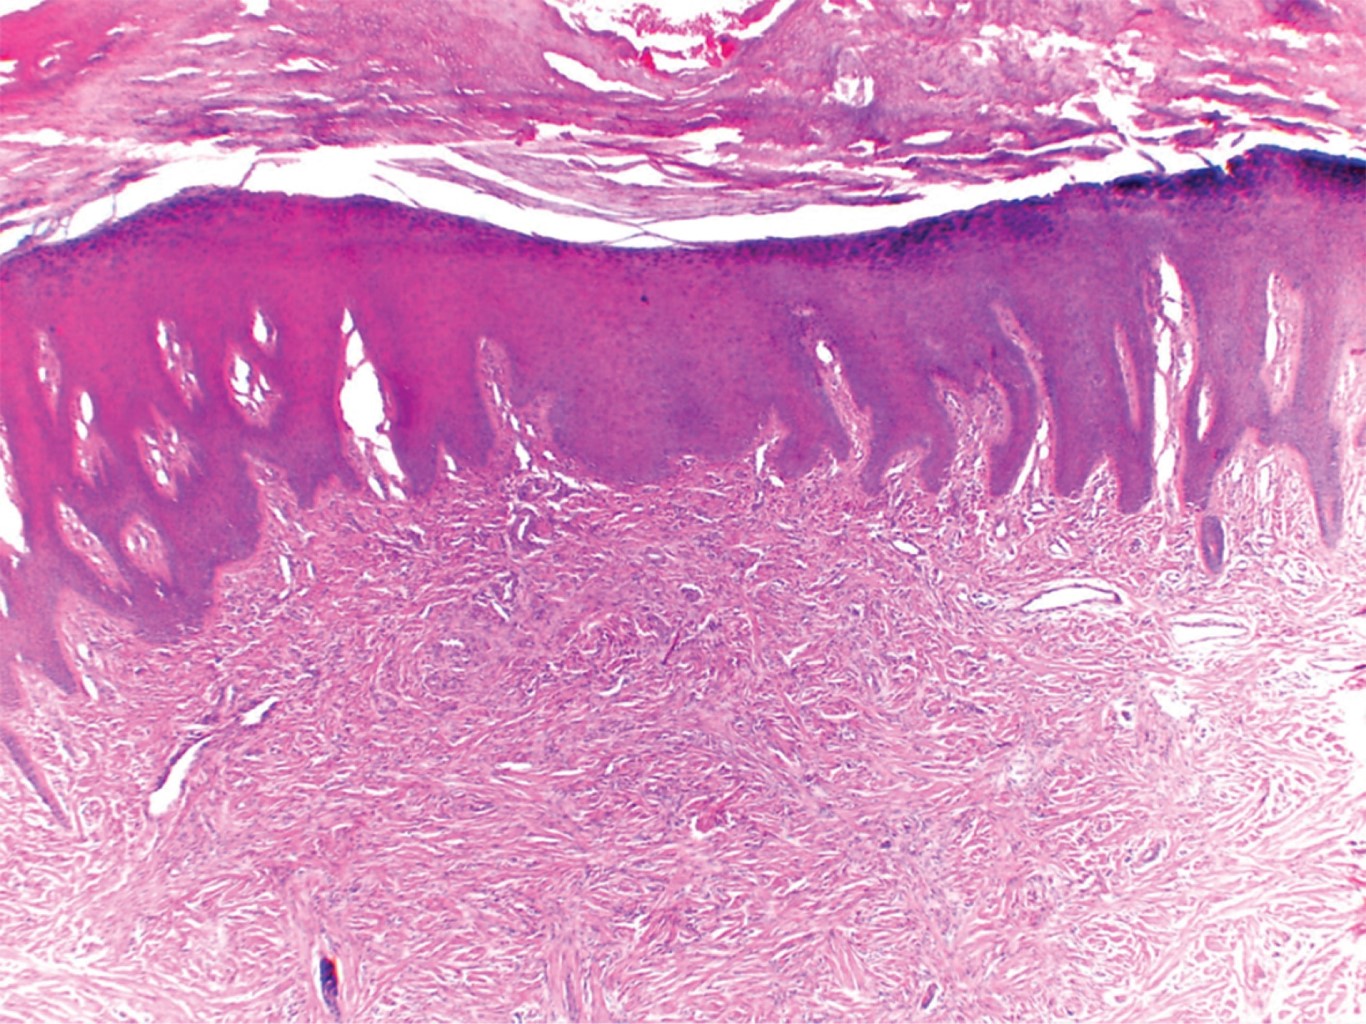

El caso corresponde a un hombre de 62 años, originario y residente del Estado de México, sin antecedentes de importancia para su padecimiento actual. Acude a consulta por una "lesión en el dedo", a decir de él, que ha crecido lentamente durante dos años. A la exploración física se observa una dermatosis localizada a la extremidad superior izquierda, la cual afectaba mano, y de ésta la cara dorsal del dedo meñique, a nivel de la falange media, constituida por una neoformación exofítica, oval, de aspecto queratósico, de 1 × 0.8 cm, de bordes bien definidos y superficie anfractuosa en algunas áreas. De evolución crónica y asintomática (Figura 1). A la dermatoscopía con luz polarizada se observa una neoformación con áreas blanquecinas centrales y escama gruesa, con eritema en su periferia (Figura 2). No había recibido tratamiento previo. Con la sospecha de un probable tumor de anexos se realiza biopsia excisional, la cual reporta: epidermis con hiperqueratosis, paraqueratosis focal, hipergranulosis y zonas con acantosis regular moderada (Figura 3), en el espesor de la dermis se observan células de núcleo fusiforme, y otras de tipo epitelioide, las cuales se entremezclan con fibras de colágena gruesa; se disponen en haces y siguen diversos trayectos (Figura 4).

HISTOPATOLOGíA

El estudio histopatológico muestra una epidermis hiperplásica e hiperpigmentada. A nivel de la dermis, se aprecian células fusiformes sin atipias, dispuestas en fascículos elongados paralelos a la epidermis, que están rodeados por estroma colagenoso o, menos frecuentemente, mixoide. En algunas ocasiones también se pueden observar histiocitos espumosos, células gigantes multinucleadas, infiltrados focales de células inflamatorias y hemosiderina. En la periferia de la lesión característicamente se observan haces individuales de colágena hialina rodeados por células tumorales.9,10 Estos hallazgos se extienden hasta el tejido celular subcutáneo.